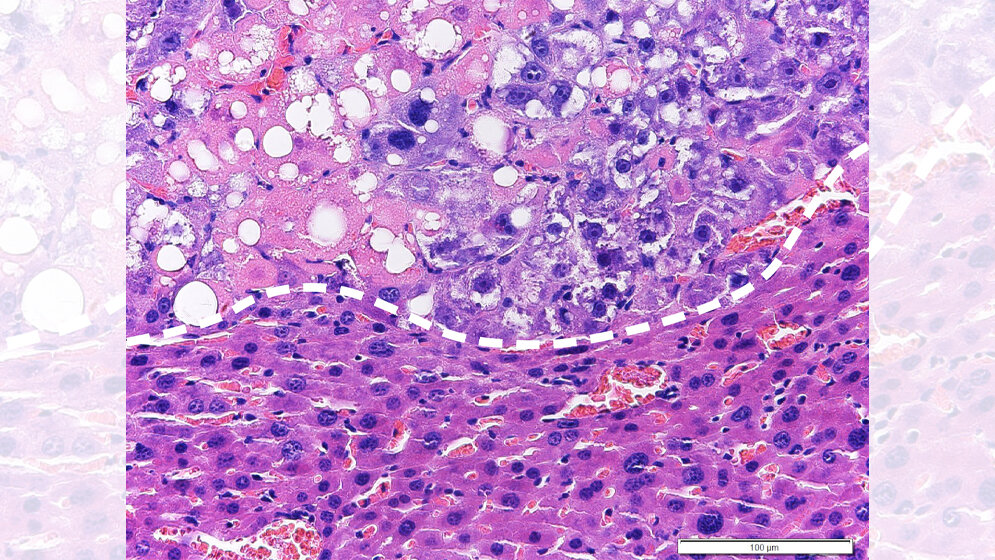

Beim neuen Ansatz wird therapeutisch in den Fettstoffwechsel der Tumorzellen eingegriffen. Durch Aktivierung des sogenannten LXRα Proteins komme es zu einer Steigerung der Fettsäuresynthese. Diese könne zunächst von der Tumorzelle toleriert werden, weil anfallende gesättigte Fettsäuren (aus der Ernährungsmedizin auch als schlechte Fettsäuren bekannt) kontinuierlich durch das Enzym Stearoyl-CoA desaturase-1 (SCD1) zu ungesättigten (guten) Fettsäuren umgewandelt werden.

Werde jedoch gleichzeitig ein zweites Protein, die sogenannte Raf-1 Kinase, gehemmt, so komme es in der Tumorzelle zu einer Anreicherung von gesättigten Fettsäuren, welche von der Tumorzelle nicht toleriert werden könne und zum Zelltod der Tumorzelle führe. Von besonderer Bedeutung sei die Tatsache, dass das neue Therapiekonzept eine starke Wirksamkeit gegen Leberkrebs habe, welcher durch Leberverfettung (NASH) hervorgerufen wird. Klinische Studien haben gezeigt, dass diese sogenannten NASH-HCCs mit derzeit verfügbaren zielgerichteten oder Immuntherapien nur schwer zu beherrschen sind.